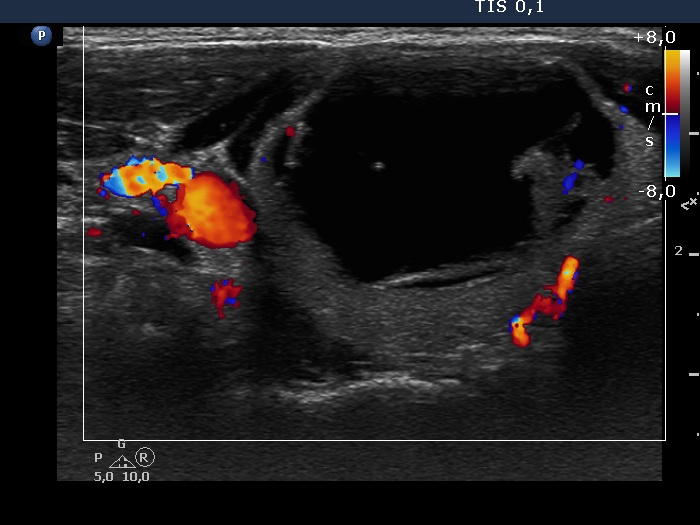

Ultrasonography. The thyroid was echonormal. The right lobe had a cystic nodule with echonormal solid components. The subtype of the cyst is difficult to define, this is probably a peripheral-type cyst.

We tried twice to remove cystic fluid from the nodule, but we have failed and only a minimal amount of thick material could be aspirated. Aspiration cytology resulted in benign cystic-colloid goiter.